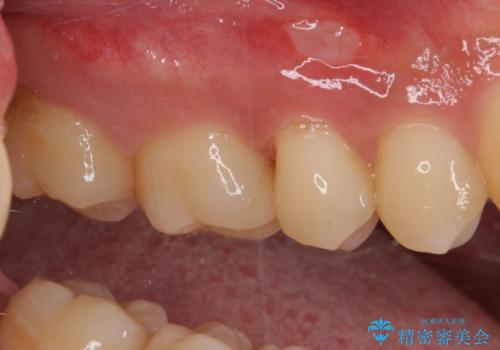

フロスが引っかかる セラミックインレーによるむし歯治療

- ウェブサイトの症例(https://seimitsushinbi.jp/case/9473/)を見て、同じようにフロスが引っかかるとのことで来院された患者様です。

虫歯を除去した後、セラミックインレーにて修復治療を行うこととしました。

セラミックインレー装着後はフロスの引っかかるストレスから解放され、患者様には大変満足していただきました。